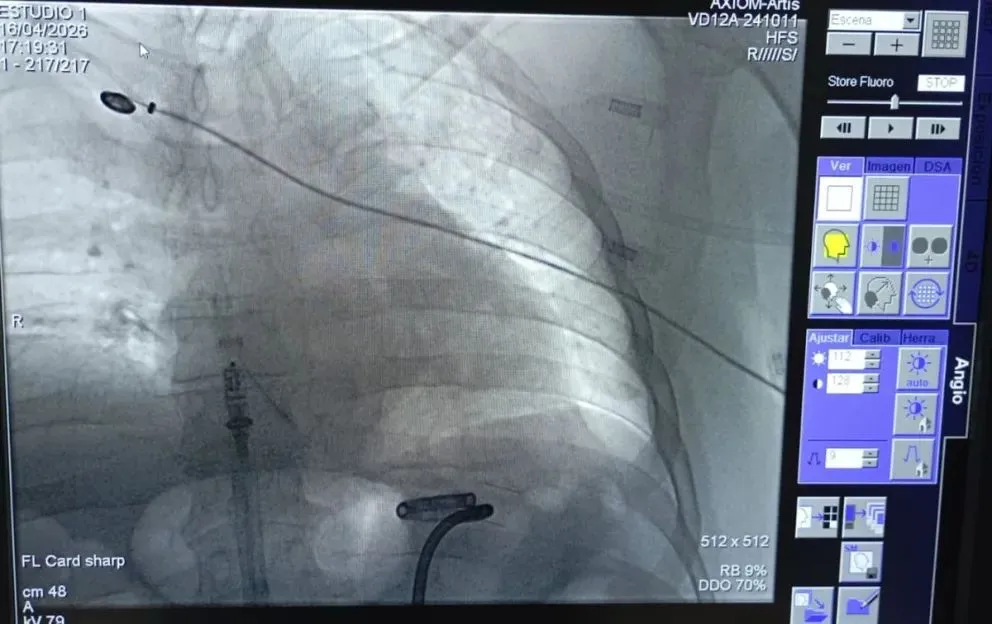

El momento en que se llevó a cabo la intervención. Foto: gentileza.

Durante una intervención de 40 minutos, un paciente recibió un marcapasos de altísima tecnología que le permitirá hacer vida común. Fue realizada por el equipo del Servicio de Electrofisiología de la Unidad de Cardiología de la Clínica Viedma.

Lee también: IPROSS pagó $231 millones y puso al día los reintegros